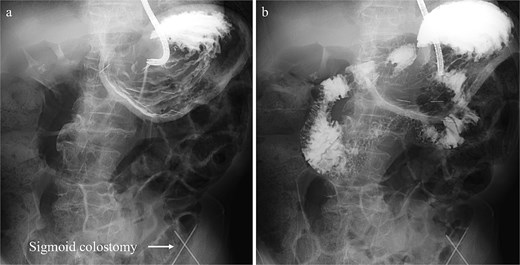

Treatment options for preventing recurrence included laparoscopic repair and percutaneous endoscopic gastric wall fixation, which were discussed with the patient and his family. Minimally invasive endoscopic suture fixation under local anesthesia was selected considering his frailty and comorbidities. The procedure was performed on hospital Day 8 using mild sedation with midazolam (2 mg) and propofol (50 mg). A GIF-XP290N endoscope (Olympus, Tokyo) was introduced with CO₂ insufflation, and upper gastrointestinal endoscopy revealed no mucosal abnormalities. The anatomical association between the stomach and the sigmoid colostomy site was evaluated under fluoroscopic guidance. Through transillumination and finger indentation, the absence of intervening organs between the stomach and abdominal wall was confirmed. Following skin disinfection and local anesthesia with 1% lidocaine, four fixation points were created using a gastrostomy fixation device (Smart Anchor®; TOP Corporation, Tokyo, Japan) with 3–0 nylon sutures at the anterior wall of the mid-body greater curvature, the anterior wall of the mid-body, the greater curvature of the angular incisure, and the anterior wall near the angular incisure (Fig. 3). Adequate separation between the stomach and the sigmoid colostomy and smooth duodenal passage were confirmed on Gastrografin contrast (Fig. 4); the procedure was completed without complications.

Gastrografin contrast study performed immediately following percutaneous endoscopic gastropexy, (a) fluoroscopic image displaying the normal anatomical location of the stomach with adequate separation from the sigmoid colostomy. (b) Fluoroscopic image showing smooth passage of the contrast medium through the duodenum into the small intestine.